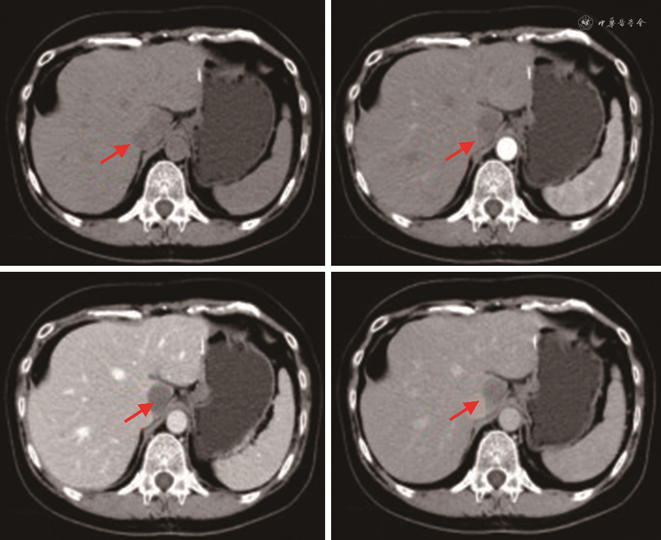

患者第1次出院后未进行药物治疗,定期在我院或浙江大学医学院第一附属医院复查肝胆B超和(或)上腹部CT,均未发现明显异常。上腹部CT平扫+增强(2018-04-19)影像所见:肝右叶部分切除术后,肝左叶低密度结节影,范围约34 mm×52 mm,边界清;平扫CT值约32 HU,延迟期边缘呈结节样轻度强化,病灶有缩小(图2)。影像诊断及建议:肝右叶部分切除术后;肝左叶占位,血管内皮瘤可能性大,其他病变不除外,请结合临床必要时进一步检查。患者于2018年5月9日第2次入院,实验室检查示:肝功能正常,乙肝系列检查HBsAb48.180↑、HBcAb0.010↓,其余指标正常;肿瘤标记物中CA724 13.94↑,其余肿瘤标记物CEA、AFP、CAl99、CAl25等均在正常范围内。排除手术禁忌后于2018年5月12日行腹腔镜下左肝部分切除术,术中用超声刀游离左肝叶周围组织,用腹腔镜下直线切割闭合器分离离断左肝外叶。术后病理(本院2018-05-16)示:(左肝)上皮样血管内皮瘤(直径6.5 cm)(图3)。免疫组化B片:AFP(-)、CD31(+++)、CD34(+++)、CD19(-)、CK7(-)、CK8/18(-)、D2-40(灶+)、Vim(++)。免疫组化诊断结果:B片:AFP(-)、CD31(+++)、CD34(+++)、CD19(-)、CK7(-)、CK8/18(-)、D2-40(灶+)、Vim(++)。

患者第2次手术后同样未进行药物治疗,仅进行定期复查。全腹部CT平扫+增强(本院2020-11-06)示:尾状叶类圆21 mm×23 mm稍低密度伴轻度强化,肝裂旁稍肿大淋巴结(图4);肝右叶部分切除术后,肝左叶占位术后,请结合临床。肝尾状叶占位灶,转移瘤待排,建议进一步检查。实验室检查(本院2020-11-05)示:肝功能正常,乙肝系列检查HBsAb86.800↑、HBcAb0.010↓,其余指标正常;肿瘤标记物CEA、AFP、CAl99、CAl25、CAl53、CA724等在正常范围内。排除禁忌后于2020年11月7日行复杂肝癌切除术,术中充分暴露肝尾状叶,用超声刀、氩气刀切除肝尾状叶并予以残端止血。切除的尾状叶送病理科行术中冰冻快切病理检查,诊断为(肝脏)上皮样血管内皮瘤。病理组织学诊断结果(本院2020-11-13):(1)(肝脏)上皮样血管内皮瘤(肿块大小2.5 cm×2.0 cm;图5),伴见脉管内瘤栓,切缘阴性,送检(第7、8、9、1、3、12组)3/13个淋巴结见肿瘤细胞转移;(2)部分肝组织;(3)注:该肿瘤组织免疫组化提示CK8/18及AFP阳性,提示该肿瘤存在向上皮成分分化。免疫组化诊断结果:E片:CD31(+++)、CD34(+++)、FLI-1(+++)、CK8/18(+++)、CK19(-)。H片:AFP(+)、CD31(+++)、CD34(+++)、CK19(-)、FLI-1(++)、CK8/18(+)、D2-40(-)、Ki-67(+)15%、Vim(+++)、EMA(-)。